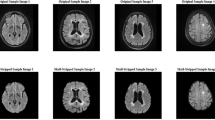

In the preprocessing stage, to eliminate the surrounding cranial bone segment of the skull from our images, could after applying the 3 × 3 median filter, use a combination of the Gabor filter and morphological operation.

After applying the Gabor filter by these parameters and morphological operators to the image, thus separating the brain parenchyma tissue from the rest of the image, and our images were ready for training the target network. Figure 1 shows all these steps for three images in general.